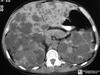

Autosomal dominant polycystic kidney disease ## Footnote CT of the abdomen (coronal reformats) demonstrates both kidneys to be markedly enlarged by innumerable cysts ranging in size from a few millimetres to multiple centimetres. These cysts also vary in density: most are near-water density, some are hyperdense, others are calcified. Also present are numerous cysts in the liver. The pancreas is unremarkable. Features are consistent with autosomal dominant polycystic kidney disease, which was subsequently confirmed.

Sigmoid volvulus ## Footnote dilation causes the classic coffee-bean sign, a pathognomonic of sigmoid volvulus.